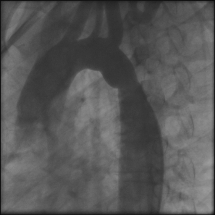

Coarctation of the aorta is a birth defect that causes a narrowing of the aorta, a blood vessel that carries blood from the heart to the rest of the body. When this condition occurs, blood flow to the lower part of the body is restricted, causing problems in blood circulation to organs such as the kidneys. The restricted blood vessel can also cause high blood pressure in the arteries that branch out from the aorta, including those in the arms and brain. This may increase risk for a stroke.

In the past, coarctation of the aorta repair involved heart surgery followed by five to seven days in the hospital for recovery. Today, heart specialists can correct coarctation in many patients without surgery, using a procedure called cardiac catheterization. In the procedure, a thin, flexible tube is threaded through a blood vessel to the heart, where it is used to insert a specially designed stent — a small, metal mesh tube — in the narrowed area of the aorta.

To perform cardiac catheterization, a tiny incision is made in the groin to insert thin, flexible tubes, called catheters. The catheters are directed through blood vessels to the heart. Catheters can carry very small instruments or repair devices, such as a stent.

The size of the restricted aorta is measured and an appropriately sized stent, or expandable metal tube, is selected. Sometimes, more than one stent is needed for the repair. Occasionally there will be a weakening of the aortic wall, called an aneurysm, associated with the narrowing. In these cases, a fabric-covered stent may be used to repair both problems. If the narrowing is too close to the head and neck vessels, stent repair may not be possible. In these cases, surgical repair is necessary and will be scheduled for another time.

The stent is placed over a deflated balloon at the catheter's tip. When the balloon reaches the site of the narrowing, it is expanded to widen the artery. The stent is left in place to support the newly widened artery walls, and the catheter and balloon are withdrawn.